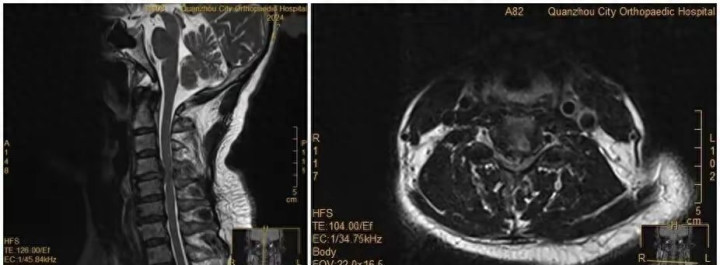

这事发生在泉州市正骨医院。接诊的杨医生说,当时片子显示她颈椎的问题特别严重,随时可能恶化。但王女士一开始死活不肯动手术,直到瘫痪才愿意躺手术台。手术很成功,但整个过程让医护团队都很着急。